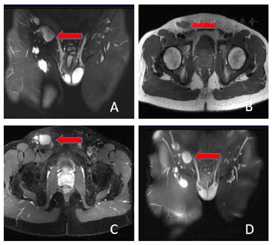

MRI影像表现:右大腿上段内侧皮下脂肪层内类椭圆形异常信号灶(图1),范围约74 mm×26 mm×87 mm,边界不清,呈浸润性生长,T1WI等稍高信号,T2WI稍高信号,T2WI/FS呈高亮信号,增强后明显强化,其内部可见夹杂脂肪信号灶。右侧腹股沟区见多发异常肿大淋巴结(图2),最大者大小约27 mm×19 mm,呈T1WI等稍高信号,T2WI/FS呈高亮信号,增强后均匀明显强化。MRI诊断:右大腿上段内侧皮下脂肪层内异常信号,良性病变多考虑,血管瘤?血管脂肪瘤?右侧腹股沟区多发肿大淋巴结,建议进一步穿刺活检。

头颈部木村病,影像学表现结合特征性的实验室检查,一般诊断不难,但当木村病发生在一些少见部分,例如四肢、腋窝、腹股沟区时,应该与相应部位的常见病变鉴别。本例报道中的发病部位比较罕见,发病形式比较有特点,表现为大腿上段内侧皮下病灶伴同侧腹股沟区多发淋巴结肿大,因两者信号特点基本一致,考虑一元论,大腿上段内侧皮下病灶表现为边界不清的肿块,T2压脂像信号高亮,无明显的囊变、坏死、出血成分,增强后明显强化,大腿病灶周围脂肪层内出现索条影或网格状浸润影,对应组织学上病灶内软组织水肿和炎症细胞的混合改变,既往几例上肢木村病的报道[3,4]也有类似影像学表现,病灶亦可包绕皮下走行的血管或神经,较大时可推压邻近肌肉,但是血管、神经及肌肉没有直接侵犯的征象,同侧腋窝也出现了淋巴结肿大,肿大淋巴结信号均匀,没有坏死。